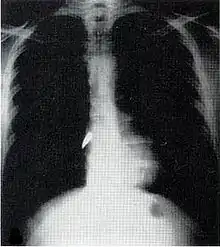

Evaluación y tratamiento

La evaluación puede ser difícil porque gran parte del daño a menudo es interno y no visible.[4] El paciente es examinado a fondo.[2] Los rayos X y la tomografía computarizada se pueden usar para identificar el tipo y la ubicación de las lesiones potencialmente letales.[2] A veces, antes de realizar la radiografía de una persona con traumatismo penetrante de un proyectil, se graba un clip más de entrada y salida de las heridas para mostrar su ubicación en la película.[2] Al paciente se le administra por vía intravenosa fluidos para reemplazar la sangre perdida.[2] La cirugía puede requerir objetos empalados y asegurados en su lugar para que no se muevan ni causen una lesión mayor, y sean retirados en un quirófano.[2] Los cuerpos extraños tales como las balas pueden ser removidos, pero también se los puede dejar en su lugar si la cirugía necesaria para sacarlos causase más daño de lo que les deja.[9] Las heridas se desbridan para elimiar el tejido que no puede sobrevivir y otro material que presenta riesgo de infección.[2]